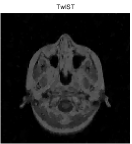

Besides the Shepp-Logan phantom image, we also tested Cameraman, Lena, Boat, Sailboat, as well as two brain images. In this experiment, we simply set and keep all other parameters unchanged. The original and the recovered images by TwIST and IADM are given in Figures 3 and 4, and detailed results including relative errors (RE), CPU time (Time), final objective function values (Obj), and the number of iterations (Iter) are presented in Table 2. It can be seen from Table 2 that IADM attained comparable or better image quality in less CPU seconds. For each test, IADM consumed more iterations while the CPU time is less because the per-iteration cost of IADM is much less than that of TwIST. Specifically, the per-iteration cost of IADM contains two matrix-vector multiplications and two FFTs, while TwIST needs to solve a TV denoising problem at each iteration. In addition, IADM always attained smaller function values. In summary, the comparison results indicate that IAMD performs favorably and can be competitive with the state-of-the-art algorithm TwIST.

| brain 1 | 52 | 14.01% | 34.25s | 4.7831e+002 | 208 | 13.64% | 20.41s | 4.5478e+002 | |

| brain 2 | 48 | 9.59% | 90.22s | 1.6397e+003 | 176 | 9.45% | 61.67s | 1.5665e+003 | |